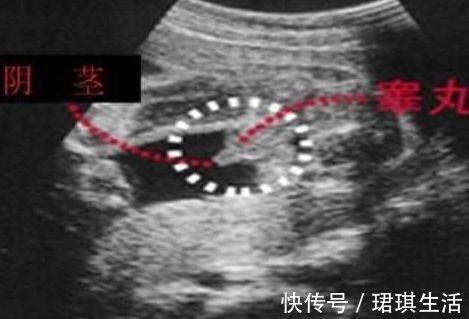

男宝宝的B超图:男宝宝的B超图上其实是能看到小鸡鸡的,图片的红圈处就是,这张图片上的小鸡鸡比较清晰,医生取的那个角度就是宝宝屁股正下方,看的很清楚。凸出的东西 是他的标记: 看到圆圆的是睾丸,如果看到圆圆的如小肠的东西就是全部鸡鸡。